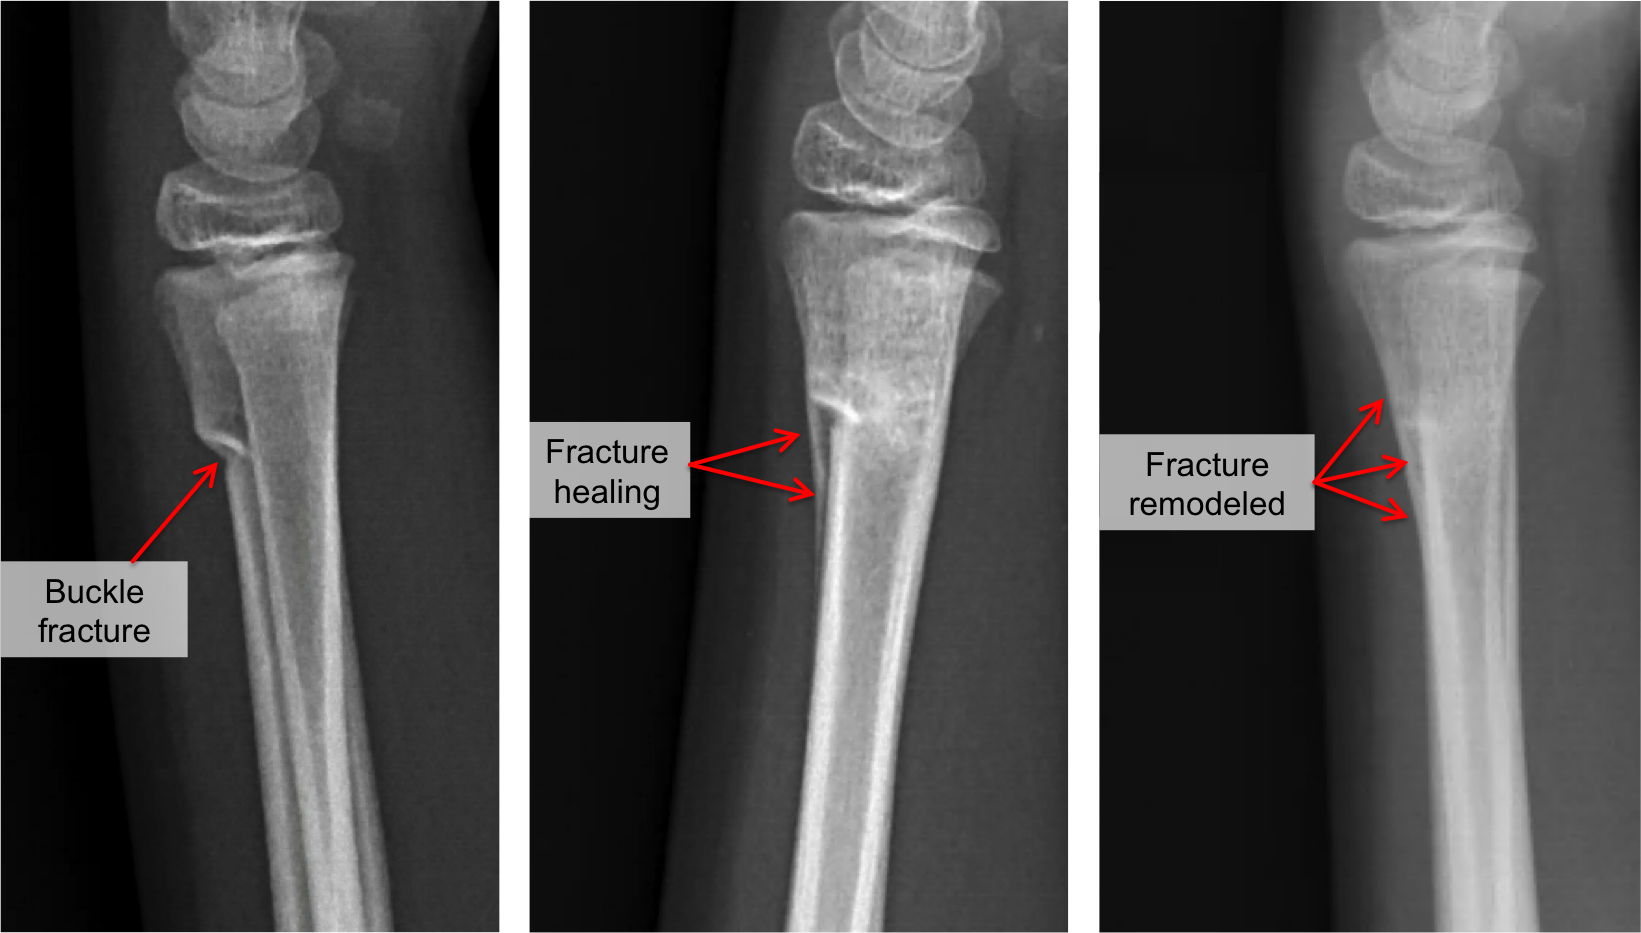

A buckle fracture in the wrist is a small area of compressed bone. Your child should wear a. Surgery may add a few more weeks to the recovery time. Both types of fractures generally heal well with appropriate treatment, often requiring. Recovery you can expect to wear a cast or.

Both types of fractures generally heal well with appropriate treatment, often requiring. Recovery you can expect to wear a cast or. Surgery may add a few more weeks to the recovery time. Your child should wear a. A buckle fracture in the wrist is a small area of compressed bone.